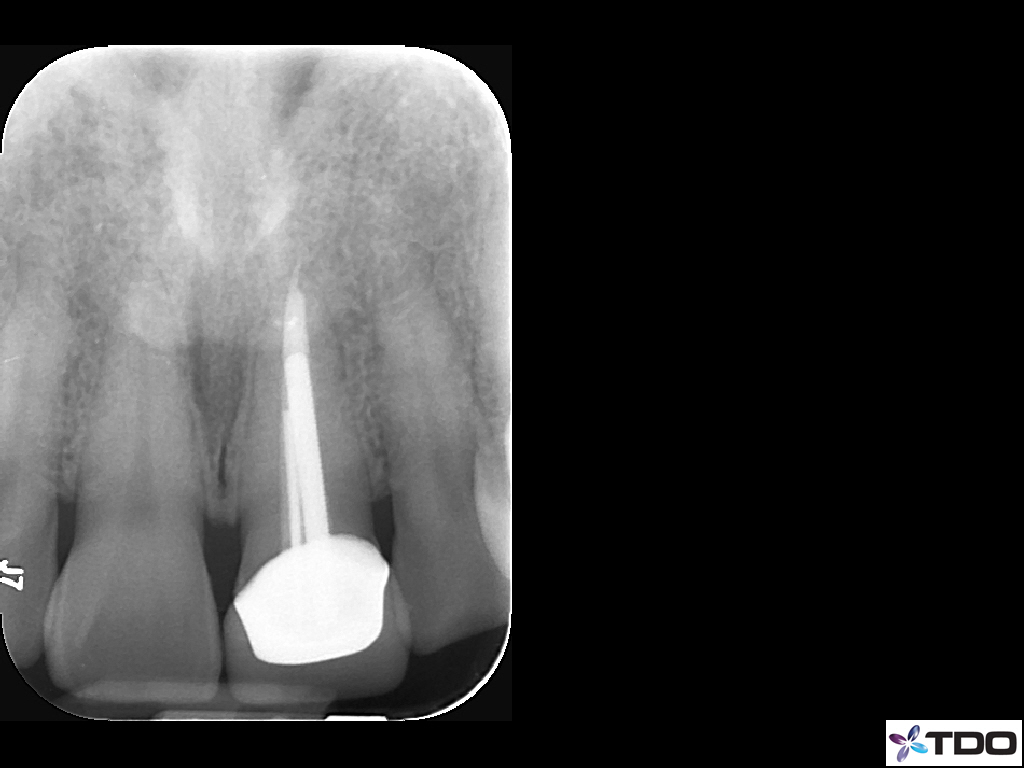

Retreatment and Repair

This patient fractured her front tooth.  The crown was only 2 years old.  Extraction and implant placement was recommended.  It would have been a challenging case esthetically.  We were able to retreat the contaminated root canal.  Posts were placed for reinforcement.  We were able to use the existing crown by retrofitting it.  We managed the occlusion to mitigate the risk of future fracture.